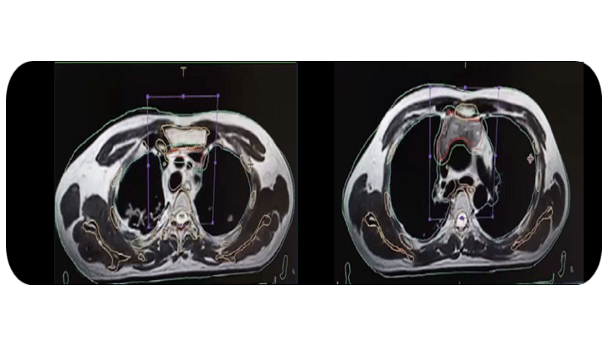

基于呼吸运动管理的调强放疗提高了剂量均匀性,减少了对正常肺组织的照射剂量。剂量、时间和效率远远优于常规调强。对于纵隔和周围肺不张的良好分辨率,可以更精准的治疗边界,同时降低周围健康组织毒性。